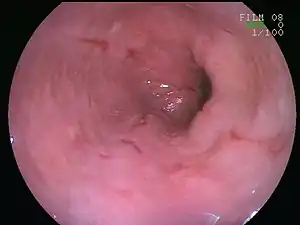

| An esophageal ulcer visualized by esophagoscopy: the reddened area at 10 o'clock on the surface of the mucosa. | |

Esophagitis can be diagnosed by upper endoscopy, biopsy, upper GI series (or barium swallow), and laboratory tests.[4]

An upper endoscopy is a procedure to look at the esophagus by using an endoscope. While looking at the esophagus, the doctor is able to take a small biopsy. The biopsy can be used to confirm inflammation of the esophagus.